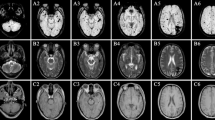

HDFM spectra from healthy and ASD children are significantly different and with high predictive value for the disease

A total of 41 children were recruited, 21 with ASD (15 Males and 6 Females, mean age 7.2 ± 0.8 yrs) and 20 with a typical development (13 Males and 7 Females, mean age 9.0 ± 0.9 yrs). Patients were admitted to the Child Neuropsychiatry Unit of the Bellaria Hospital (IRCCS, Bologna) for a clinical diagnostic assessment and a comprehensive neurological work up. Details of recruitment and diagnostic panel are described in the Methods. In all 21 patients medical, genetic and neurological comorbidity was excluded. Childhood Autism Rating Scale (CARS) total scores ranged from mild to severe autistic features, while developmental assessments showed variability from normal IQ to severe cognitive impairment (Supplementary Table 1). A small sample of fresh whole blood (500 μL), treated with ethylenediaminetetraacetic acid (EDTA) as the anticoagulant, was collected from all subjects and used for HDFM measurements and membrane lipidome analyses. Equipment settings and handling protocol for hyperspectral imaging are reported in Methods. Optical images of RBC were acquired for all samples, and for uniformity of the sampling procedure, we choose to have the prevalent RBC round shape in the optical field, excluding echinocyte and stomatocyte forms, which are known to be increased in autism7, 8, but can also depend from pH and other blood parameters, or even be artefacts during blood storage or oxidative transformations. Accurate collection of the spectral reflectance from RBCs gave rise to 8 spectra in the 430–800 nm wavelength region (Supplementary Fig. 1). It is worth noting that, using a small spectral angle (0.1 in radians), the 8 spectra satisfactorily gave a fingerprint of the Region of Interest (ROI), with optimal coverage of the optical image (>98%) as shown in Fig. 1 (see Supplementary Figure 1 – panel A – for the original HDFM spectra before the smoothing procedure). We were also aware that the cell membrane curvature, determined by the orientation of the blood cells relative to the propagation vector of the illuminating electro-magnetic field, could have a significant influence. When a biconcave shaped RBC interacts with a linearly polarised light beam tends to orient its long axis in the direction of the electric field of the incident beam, due to RBC’s intrinsic birefringence. In our case, the light source was an unpolarized halogen light source, so no “forced” orientation of the cells was observed. The lamp normalization routine was used in order to eliminate the background light, ameliorating the results obtained by the method previously reported by us17. Under these careful set-up conditions, we constantly obtained a good match by mapping of the 8 end-members spectral library with the small spectral angle onto images taken from different blood samples. Therefore, we could conclude that the identified spectral signatures are not sensitively affected by the cell orientation, but probably result from a particular curvature of the membrane surface connected to the morphological status. Indeed, the cell orientation dependency could be observed when differently shaped RBCs are examined, such as stacked RBCs forming roleaux and echinocytes, giving rise to different spectral end-members17, that are currently under investigation for the biological importance of these changes.

RBCs optical images and the corresponding hyperspectral image for healthy (left panels) and ASD (right panels) children. In yellow box a selected RBC for which an enlarged view is given below, where it is clearly seen the satisfactory matching of the optical and hyperspectral images. Coloured areas indicate regions whose reflectance spectra match with the spectral end-members of the library, as shown in Supplementary Fig. 1.

The spectral distribution of the eight HDFM end-members in the control samples is shown in Supplementary Fig. 1S (panel A); in Supplementary Table 2 the spectra 3, 4, 5, 6 are reported as mean values ± standard error of the mean (SEM) of two independent acquisitions for each sample. The other four spectra, namely 1, 2, 7, 8, were found to have large errors therefore they are not reported in the Table, but only their total spectral distributions are reported for ASD and healthy children in the footnote. The optical imaging with spectral matching of the library in representative RBCs of both control and patient groups are shown in Fig. 1, left and right panel, respectively. Figure 2 in the main text reports the eight histograms with the error bars of the control (dark grey) and ASD (light grey) groups. The HDFM spectrum 4 is reported in Fig. 3, and its distribution between control and ASD subjects was significantly different (Fig. 2 and Supplementary Table 2).